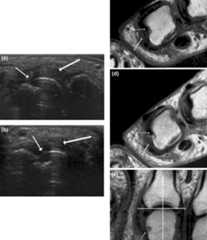

Ultrasound and MRI findings in RA:

(a) (b): Signs of destruction and inflammation on ultrasonography

(c) (d) (e): Magnetic resonance imaging showing 2nd MCP joint in a patient with established RA.

(thin arrows indicate erosive change; thick arrows indicate synovitis)